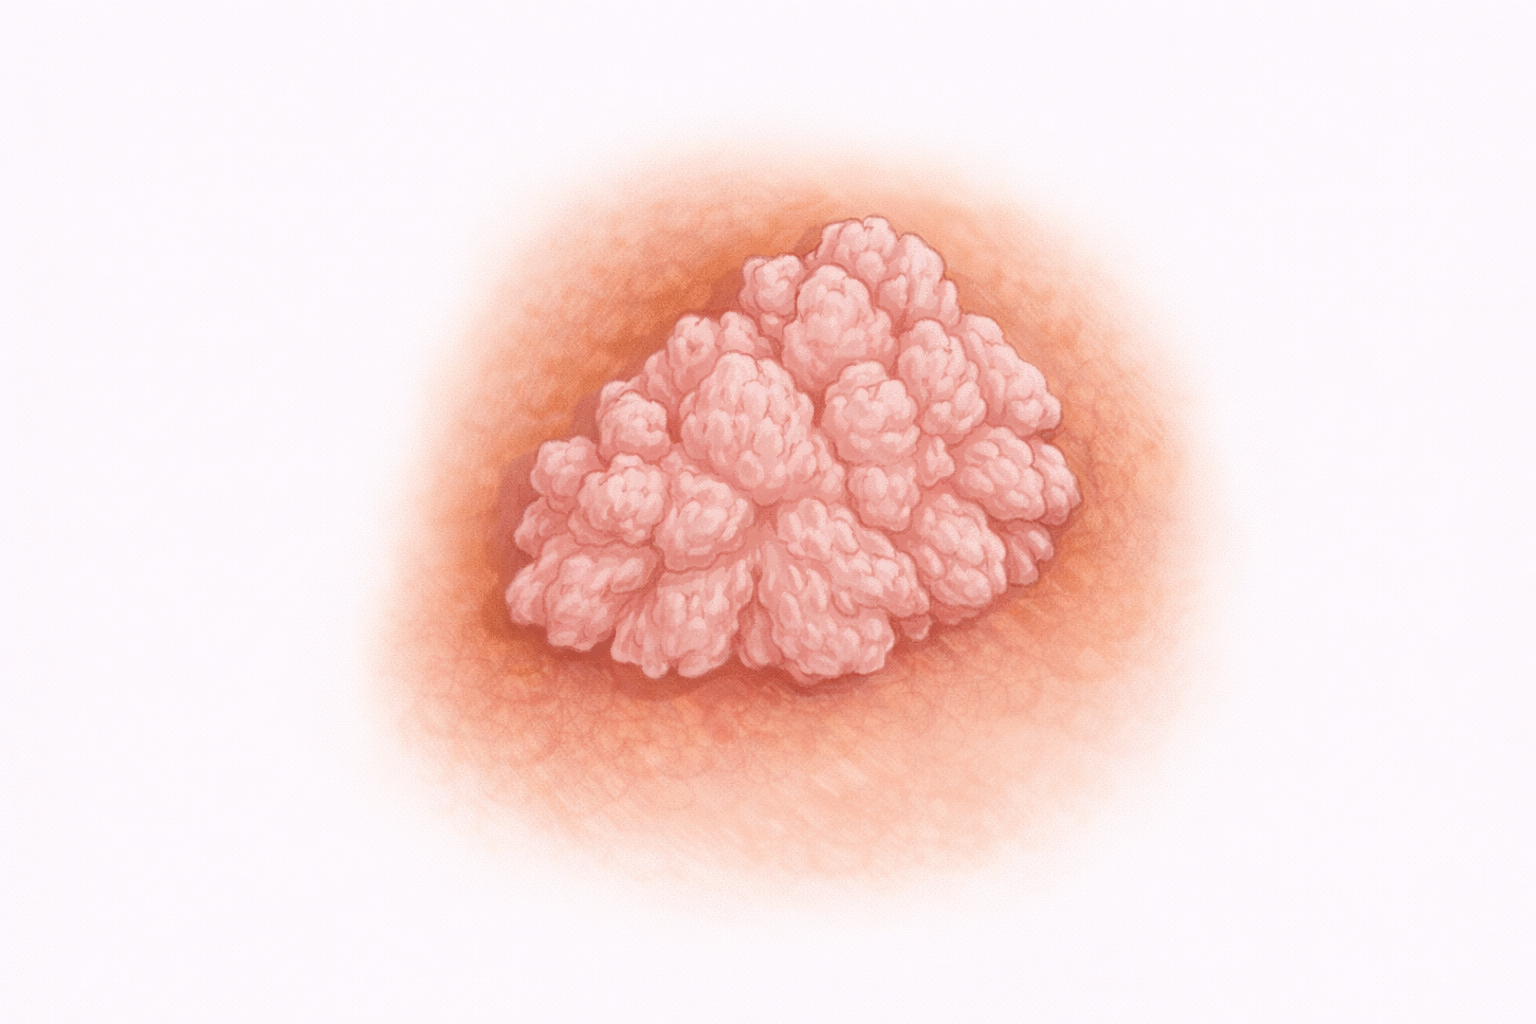

Condilomas

Síntomas

En fases iniciales pueden ser asintomáticos y detectarse únicamente al examen físico.

Los síntomas más frecuentes son:

- Aparición de pequeños bultos o verrugas en la zona anal.

- Picor persistente.

- Sensación de humedad o secreción.

- Molestias al sentarse.

- Pequeño sangrado si se irritan o traumatizan.

En casos de mayor tamaño pueden causar sensación de cuerpo extraño o dificultad para la higiene.